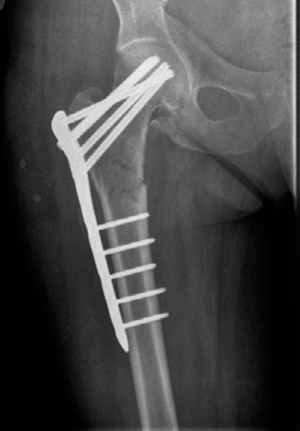

A 78-year-old woman fell out of her bed and sus- tained this injury. She is in reasonably good health and independently mobile, able to care for herself and do her own shopping. (Figure 8.9.)

CANDIDATE : This is an AP radiograph of the right hip showing a reverse-obliquity inter-trochanteric fracture with subtrochanteric extension. The lesser trochanter is proximally displaced with loss of the medial buttress. I would like to see a lateral radiograph, however, based on just the AP view, it is an unstable fracture pattern.

My management for this patient would start with a thorough assessment and optimization of her general medical condition. We need to exclude the possibility of pathological fracture, although the available radiograph shows no evidence of that.

I would obtain full-length radiographs of the femur. Provided she is fit and agrees to surgery, I would aim to manage this fracture operatively and I will do so as early as possible, preferably within

36 hours of admission [new NICE guidelines]. I would use a cephalomedullary device as this has shown better results rather than fixed-angle plating devices in this fracture configuration.1,2